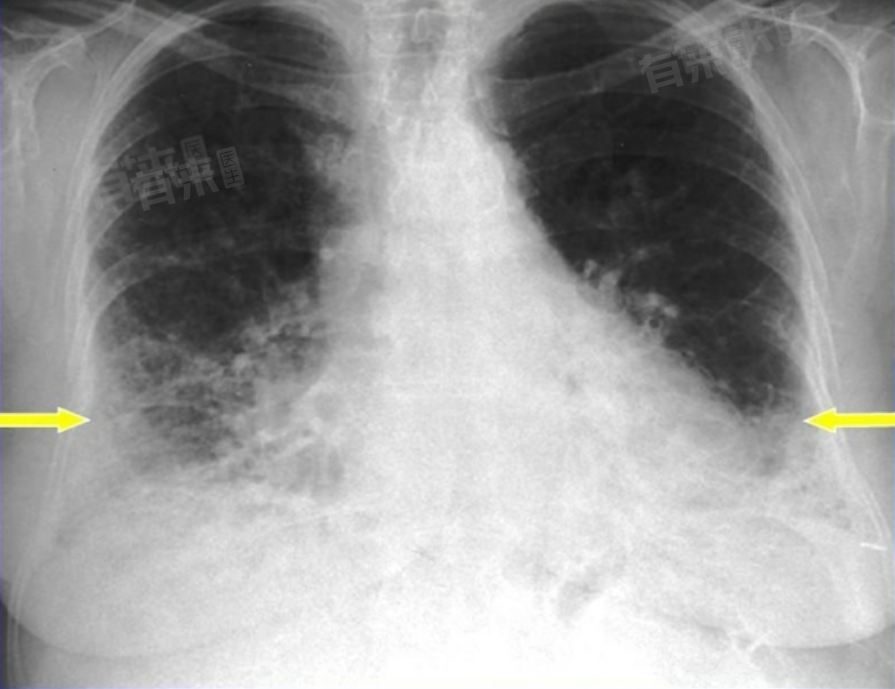

肺纤维化的引发原因多样,环境中的有害物质长期侵袭,身体内部疾病的发展,甚至一些特殊的遗传因素,都可能促使肺组织纤维化。

肺纤维化成因复杂,涉及多方面因素。若有自身免疫性疾病,需积极治疗控制病情。有家族遗传史者,更要定期体检。早发现、早干预,对延缓肺纤维化发展意义重大。